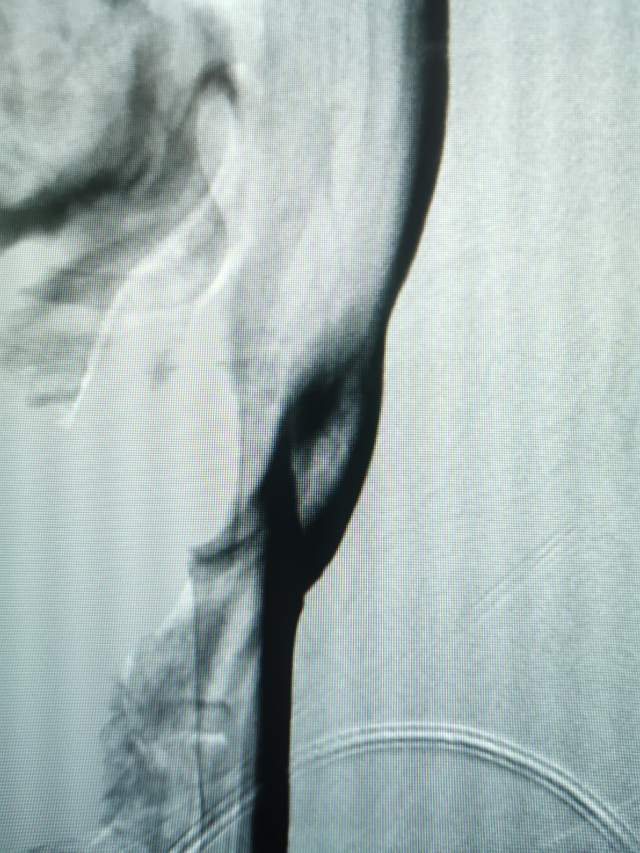

术后,紊乱的血流变得圆滑自然,血流快速丝滑通过左侧颈内动脉起始部,单位时间通过单位横截面的有效血流量增加,有利于改善低灌注,也有效防止了泥沙样栓子脱落。

术后次日查房:患者自诉头晕改善。此外,患者最大的感受就是计算力明显改善,感觉数学题好简单了。原来100-7等于是多少不会算,术后问:100-7等于多少,患者脱口而出,正确说出93,别的算数也是溜溜的了。患者头晕和计算力的明显改善,进一步证明了我们的外科干预是及时的和妥当的。